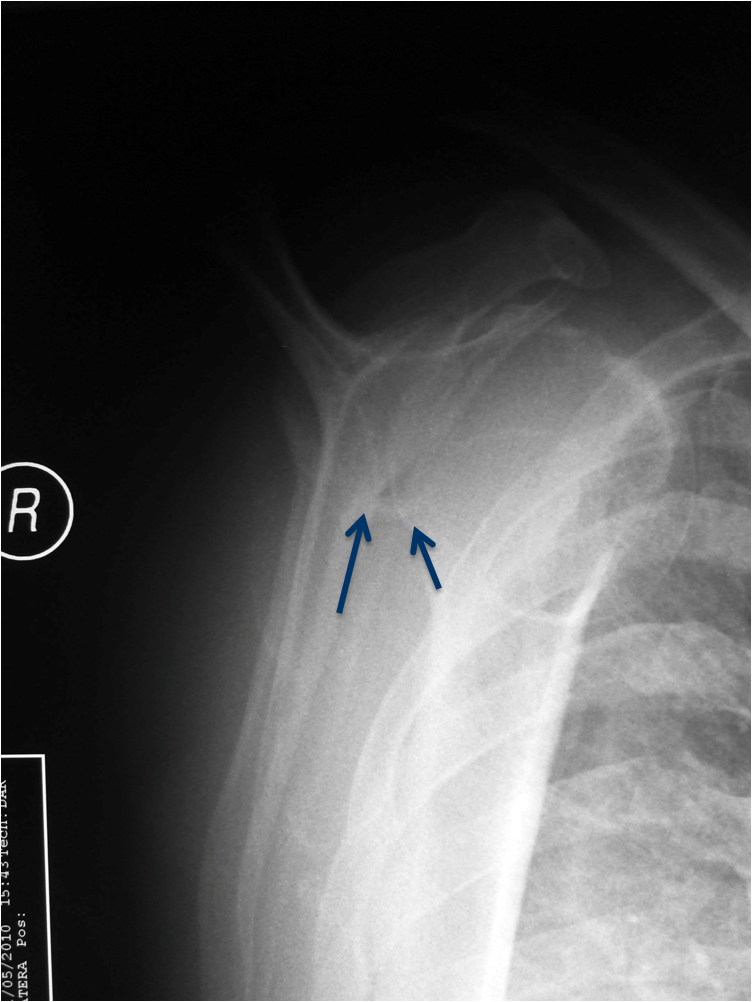

This is an example of a patient with an anterior shoulder dislocation. The bony Bankart lesion can be seen (arrows).